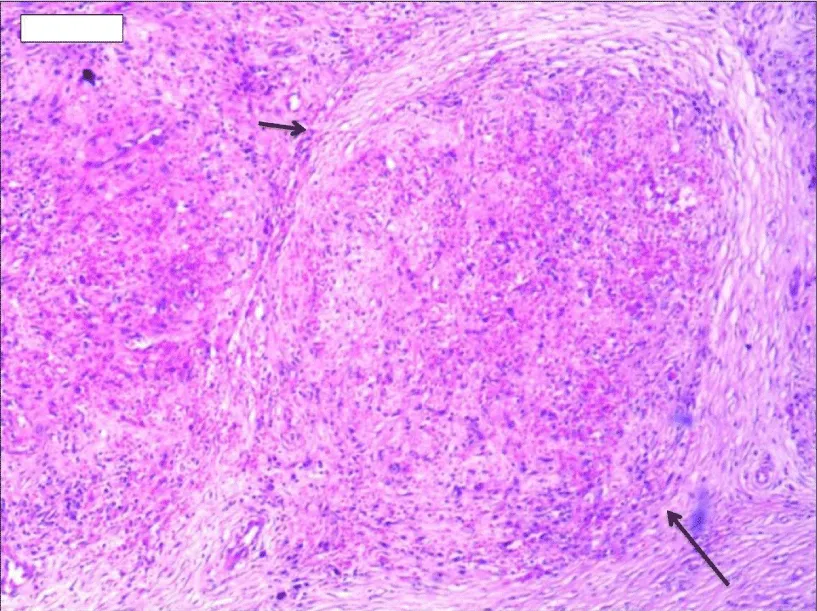

Solitary well-circumscribed masses were detected in all the five patients by ultrasound. One mass was of hypoecho, while the remaining masses were of hyperecho with posterior enhancement (Figure 1A). The maximum diameter ranged from 3.0 cm to 9.0 cm. At CT scanning, two masses appeared as hypodense (Figure 1B) and one was isodense (Figure 2A) to the normal spleenic parenchyma. In the two patients who received MR imaging, masses were isointensity at T1 weighted images (Figure 3A) and hypointensity with scattered sign void spots at T2 weighted images (Figure 3B). After intravenous injection of the contrast materials, all the five masses presented circle enhancement at arterial phase (Figure 3C and Figure 4A), while peripheral enhanced node was noted in one mass (Figure 2B). The circle enhancement persisted and radical line enhancement were observed at portal vein phase in 3 cases (Figure 1C) and progressive filling in was seen in two cases (Figure 2C). At delay phase of MR imaging, one lesion showed obvious enhancement with stellate low signal scar in the center comparing with surrounding splenic parenchyma (Figure 3D), while the other demonstrated central and circle enhancement to form a spoke-like appearance (Figure 4B). At delay enhanced CT scanning, two masses were isoattenuation to the surrounding splenic parenchyma (Figure 2D) and one lesion kept as hypoattenuation but with radial enhanced lines and enhanced circle to form a spoke-like appearance.

At pathological examination, all the masses were well demarcated on gross cut surface. A central stellate scar with peripheral interspersed dark brown nodules and the whitish intervening fibrous bands was noted to form spoke-like appearance (Figure 3E), which was well correlated with CT and MR imaging findings at enhancement. Microscopically, these angiomatoid nodules were surrounded by dense concentric collagen fibrous stroma and dispersed stromal cells with oval-to-spindle nuclei and scanty cytoplasm (Figure 3F). The abunden fibrous stroma may result in hypointensity at T2 weighted MR images. Hemosiderin was noted in the angiomatoid nodules (Figure 3G), which might contributed to signal void at T2 weighted MR images.